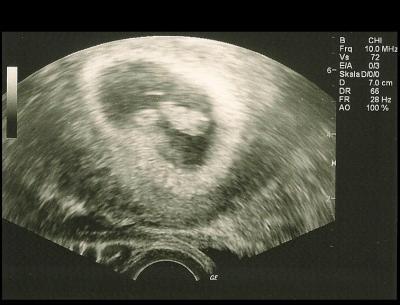

Hallo zusammen, wollte euch kurz von meinem FA-Termin heute berichten. Bin jetzt 7+5, das Baby war 1,6 cm groß, was 7+6 entspricht. Also zum Glück alles gut. Jetzt bin ich erstmal wieder erleichtert. :-)

Bild zu FA-Termin heute + US-Foto - Forum für April - Mamis

oh wie toll. du, auf den ersten blick dachte ich, es sind zwillinge lg steffi

da is so viel drin, das sieht tatsächlich nach 2 Kiddies aus. Aber es ist so unscharf. Hat der Arzt über die Bauchdecke geschallt?

Nein, war ein vaginaler Schall. Aber das kleine Bild ist immer besser als dann das große eingescannte. Und mein FA wackelt im Moment des Abspeicherns immer rum. Die Bilder am Monitor waren sehr viel schärfer. Egal. :-)